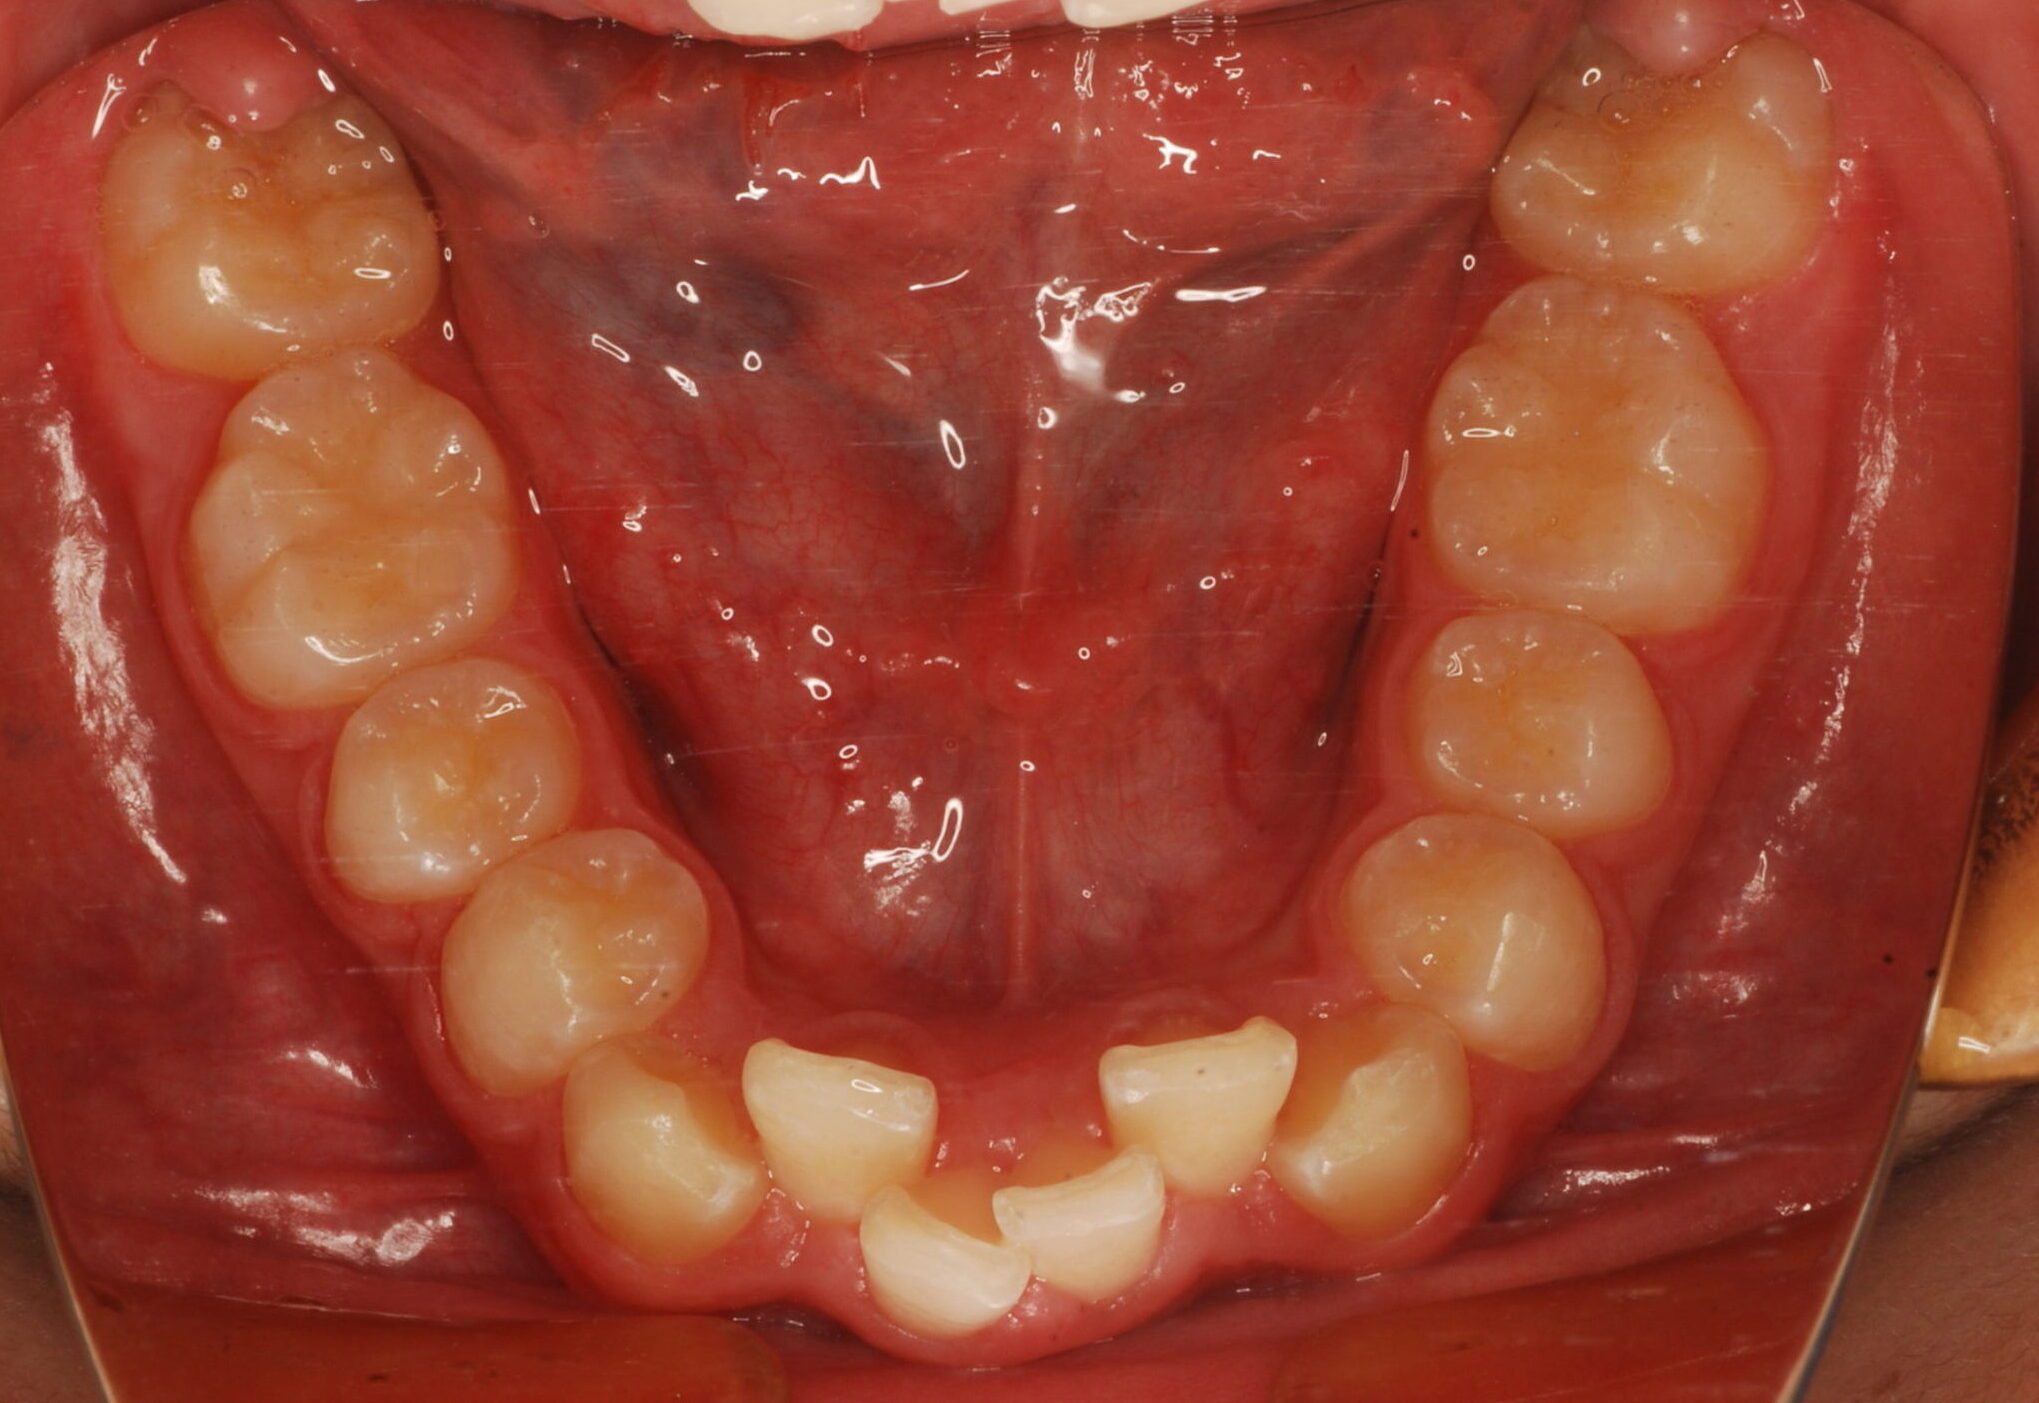

治療前

【診断】叢生、過蓋咬合

【治療方法】上下両側第一小臼歯抜歯、ワイヤー治療期間3年間、上顎口蓋にTPA(トランスパラタルアーチ)を行いました。